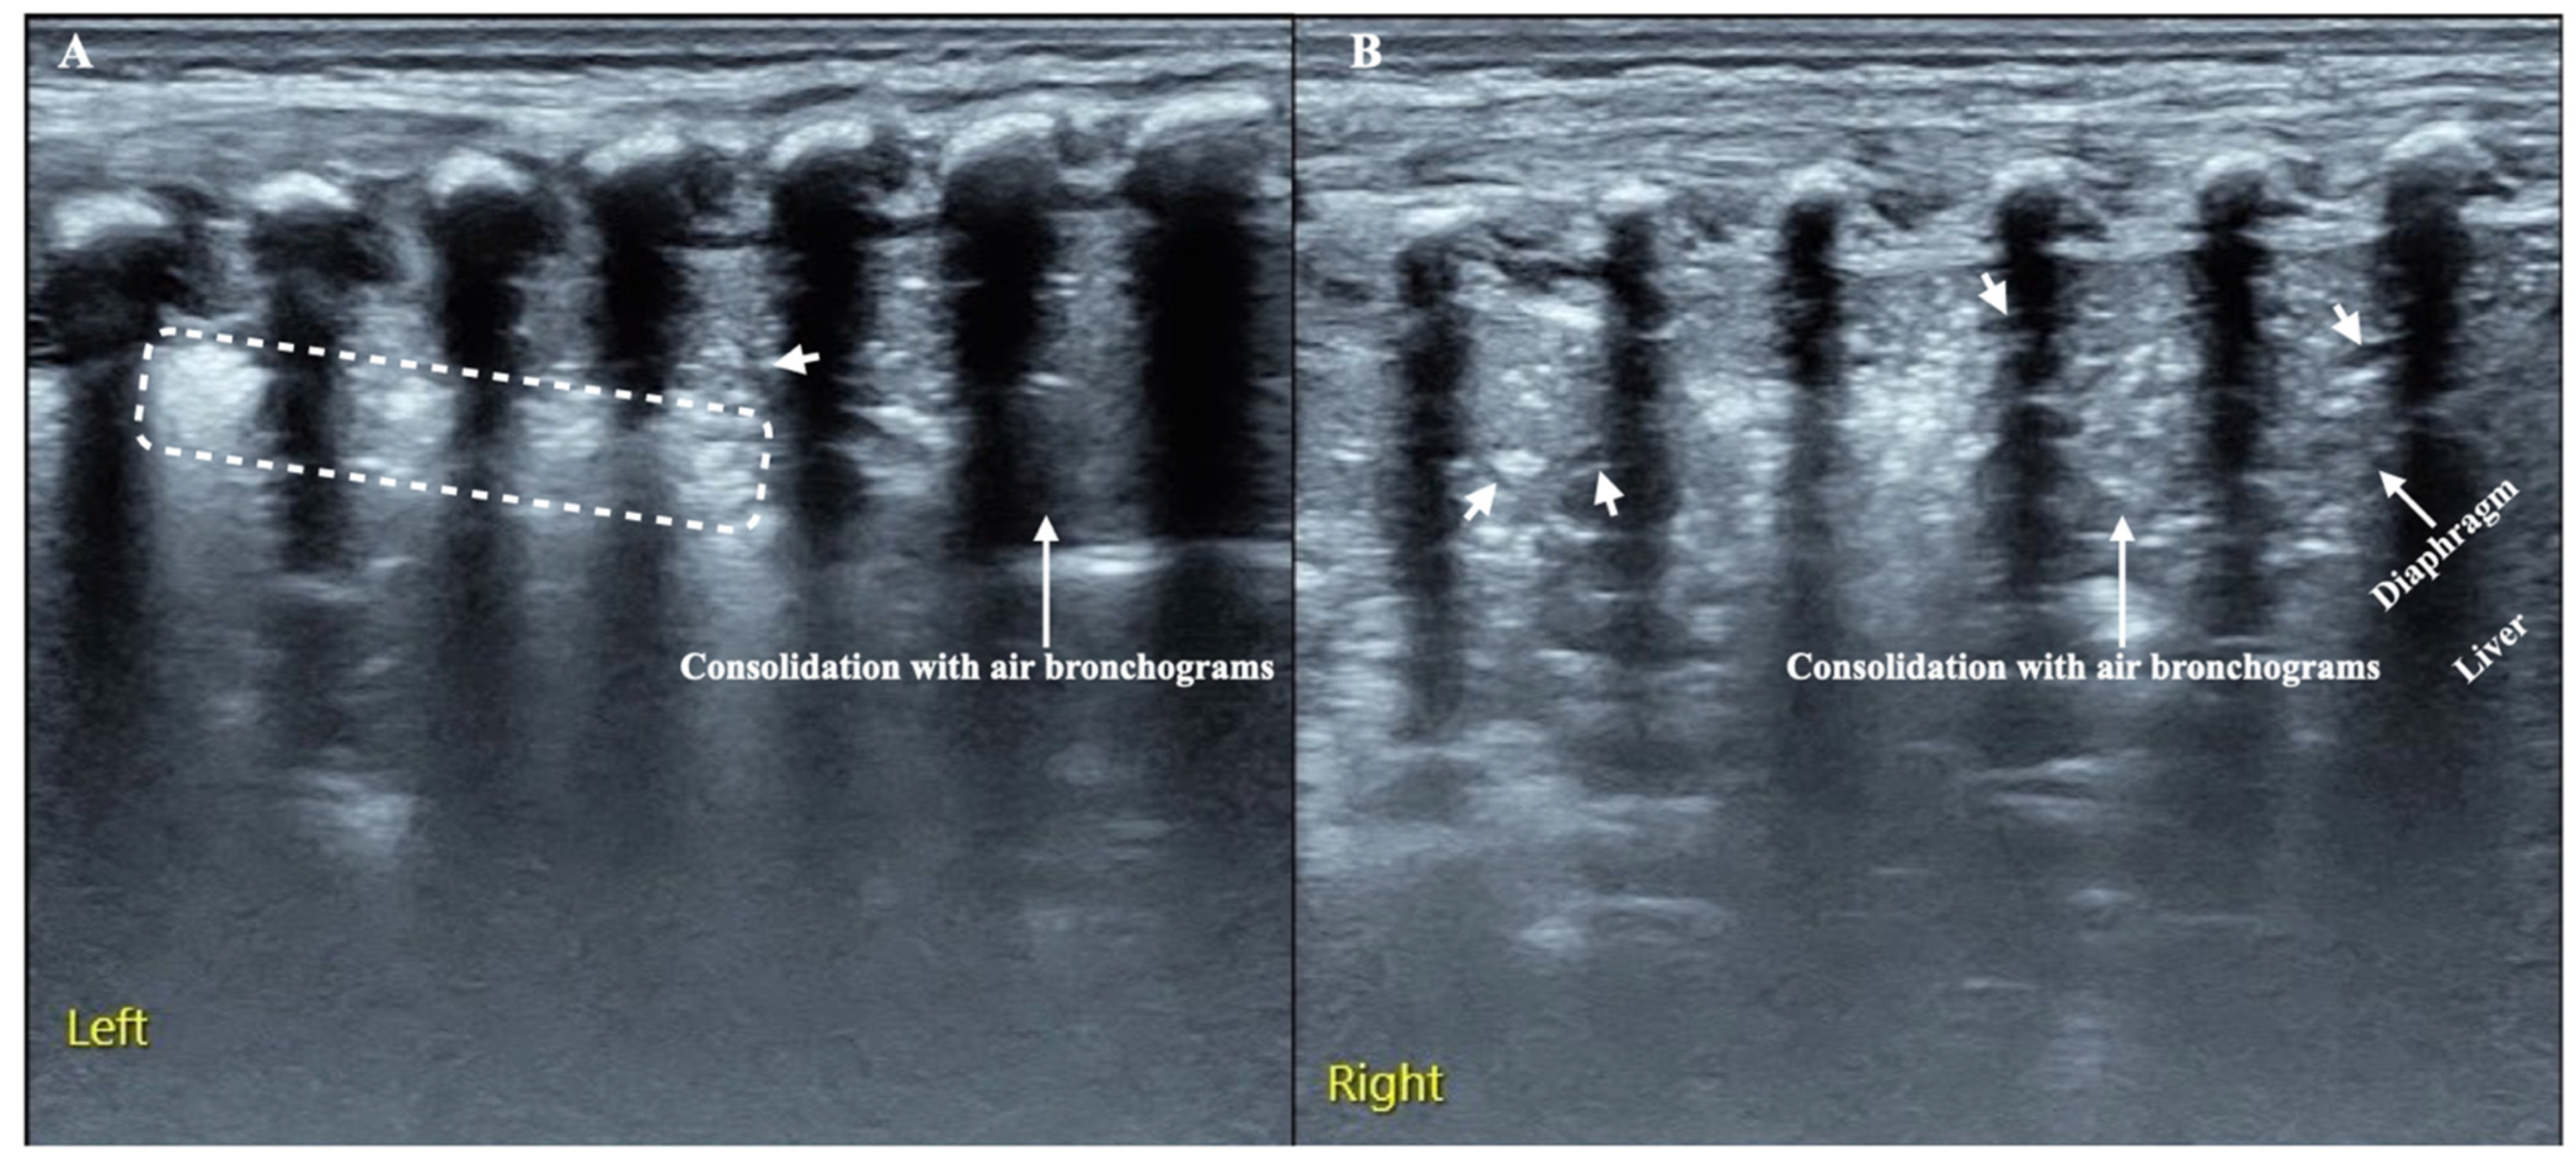

3.3. LUS Findings of FP

3.4. Typical Case Presentations